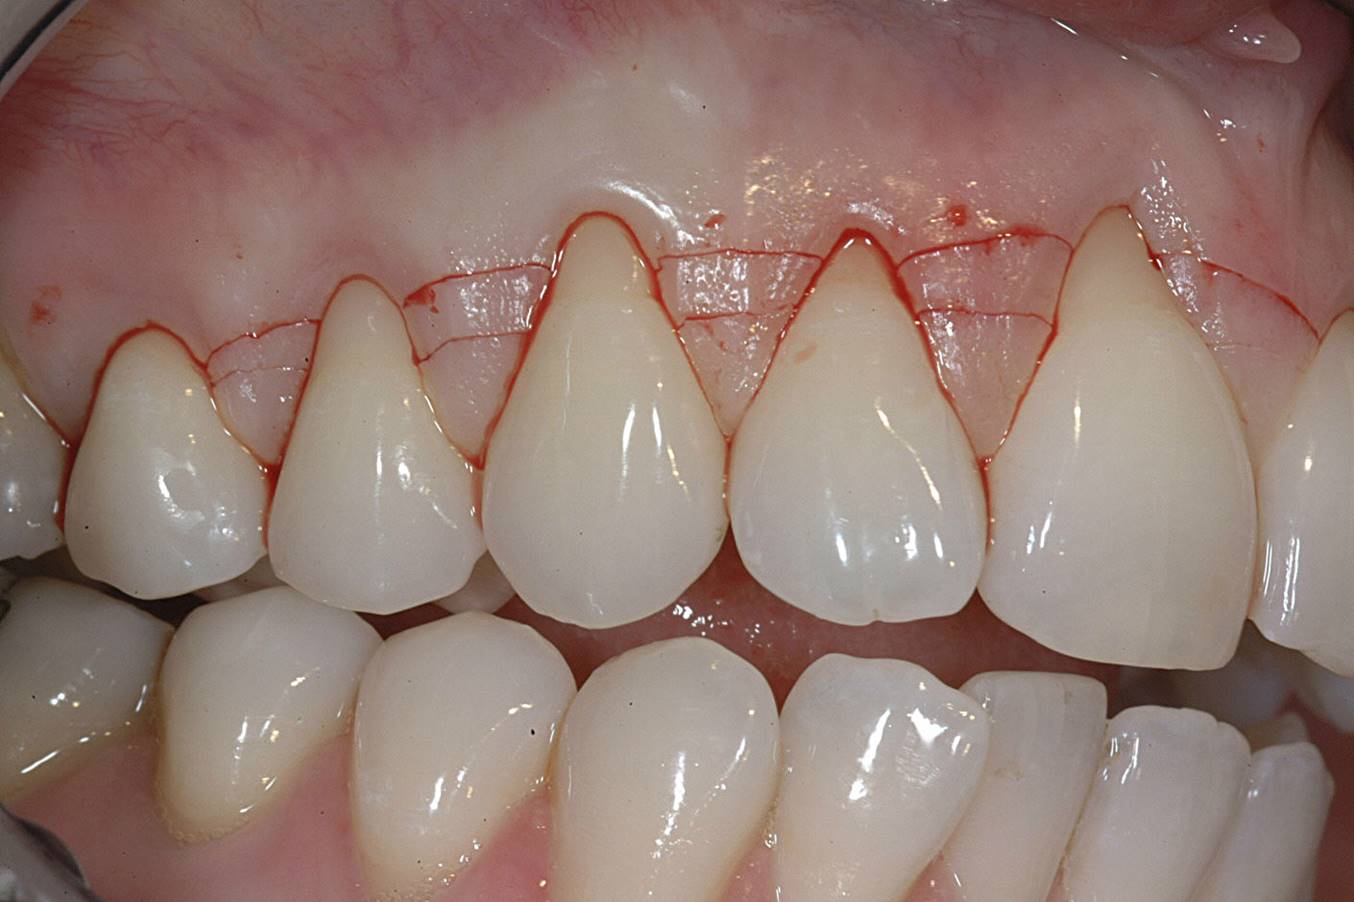

The CTG was then harvested from the palate as previously described and placed over the roots (Figure 11). The primary flap was advanced to cover the graft; a dual blood supply was assured from the underlying tissue and the overlying flap. Atraumatic suturing was performed using fine sutures (eg, Resorba® 6-0/7-0 Resolon™, Osteogenics Biomedical, osteogenics.com) to approximate the flap margins.

After 1 week, rapid healing and good closure were observed. After 2 years, complete root coverage was visible, a thicker alveolar housing was achieved, and the gingiva was more resistant to future breakdown (Figure 12).